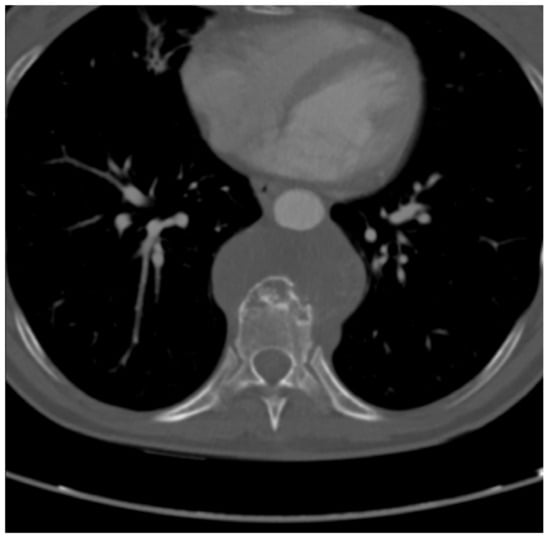

2.2. Imaging Studies